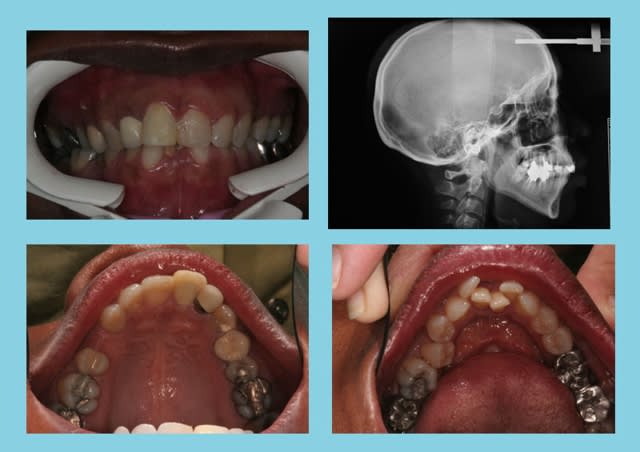

Sexe : F

Age 45 ans

PHOTOS

Debut 1 bwsjpt - Eugenol